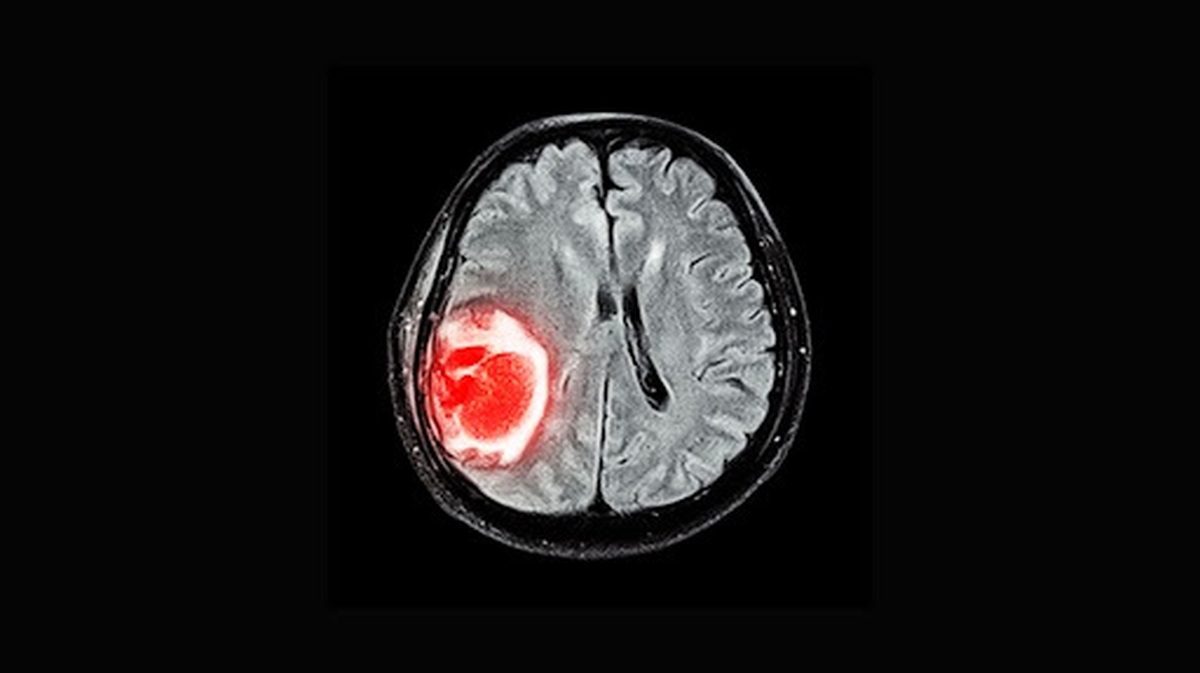

محققین روس موفق به‌ساخت ریزذرات مغناطیسی شدند که با اسید تانیک پوشیده‌اند که توسط سلول‌های توموری در محیط آزاد می‌شوند و شناسایی سریع و دقیق تومورها را امکان‌پذیر می‌کنند.

به گزارش مجله تیتر ۱۲ به نقل از برنا؛ محققین روس موفق به‌ساخت ریزذرات مغناطیسی شدند که با اسید تانیک پوشیده‌اند و به دلیل واکنش سریع نسبت به اگزوزوم‌ها (Exosome) و وزیکول‌هایی (Vesicle) که توسط سلول‌های توموری در محیط آزاد می‌شوند، شناسایی سریع و دقیق تومورها را امکان‌پذیر می‌کنند.

در گذشته، سریع‌ترین روش شناسایی تومورها، چهار ساعت زمان می‌برد ولی استفاده از این ریزذرات جدید، این زمان را به نصف کاهش می‌دهد. این ریزذرات در چارچوب پژوهشی که با حمایت مالی برنامه بنیاد علوم روسیه (RSF) انجام پذیرفته است، تولید شده‌اند.